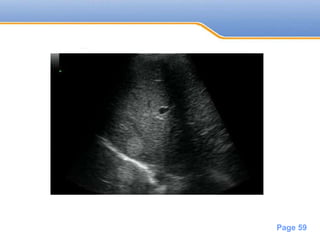

• #59 Innumerable lesions are seen throughout the liver, appearing mildly hyperintense on T2 imaging and hypointense on precontrast T1 imaging with progressive rim enhancement on arterial-phase and portal-venous-phase imaging. In addition, there is a distinct 2-cm mass within the posterior aspect of the right lobe of the liver (yellow arrow). It is moderately hyperintense on T2 imaging and hypointense on precontrast T1 imaging. The lesion shows subtle peripheral discontinuous nodular enhancement that progressively fills in on subsequent imaging with homogeneous signal that matches the blood pool at 6 minutes. Ninety-minute delayed hepatobiliary-phase imaging demonstrates isointensity of this single lesion with the blood pool. All other lesions appear hypointense relative to the liver, with a hypointense rim and isointense ring within the lesion in a characteristic target pattern. The colorectal metastases in this example are highly typical: mildly hyperintense on T2 with slow rim enhancement on dynamic-phase imaging. The target appearance seen on the delayed hepatobiliary phase is also typical of metastases. The presence of a both cavernous hemangioma and colorectal metastases in the same patient presents an opportunity for direct comparison of the appearance of these lesions on both T2 and contrast-enhanced T1 imaging. As seen in previous examples, the signal within hemangioma follows the blood pool on steady-state imaging (beyond a few minutes).